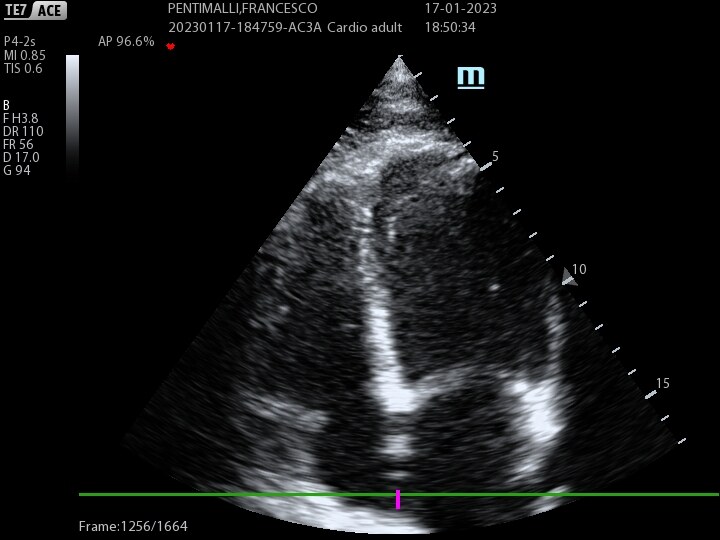

Echocardiogram color-doppler

Een transthoracaal color-doppler echocardiogram is een veilig en niet-invasief echografisch onderzoek...